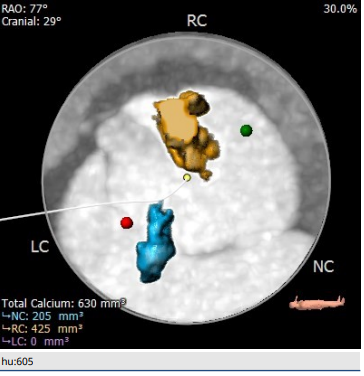

钙化分析

术前陈晓敏教授带领团队对这位患者进行了详细的分析,从CT分析结果显示,患者主动脉瓣为type 0型二叶瓣,瓣环直径为24.4mm,结合患者瓣叶钙化等情况,符合美敦力Evolut PRO 29mm瓣膜选型。经讨论决定以右侧股动脉为主入路,左侧股动脉为辅入路,术中进行23mm球囊预扩张,保证系统顺利跨瓣及释放,并采用世界先进的Cusp Overlap技术植入瓣膜 ,以更精准地释放瓣膜深,减少对患者传导系统的影响。